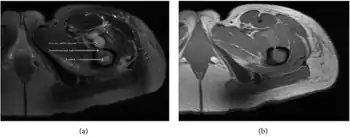

| a,b) MRI showing the Brodie's abscess in the left proximal femur | |

Axial T1-weighted MRI pre-contrast enhancement showing that the intramedullary collection is T1-hyperintense suggesting proteinaceous viscous fluid consistent with infection. -

Axial T1-weighted fat-saturated MRI image following IV gadolinium contrast demonstrating the intramedullary lytic area seen on radiography to be ring enhancing consistent with a purulent fluid collection. Extensive circumferential periosteal enhancement is noted. There is also substantial bone marrow enhancement. -